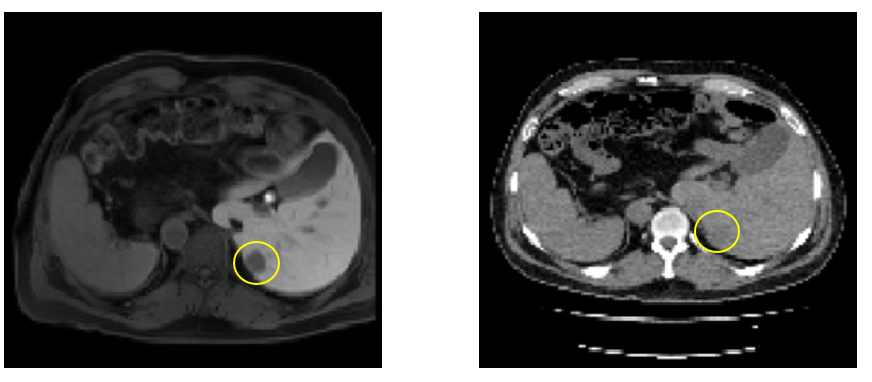

Hepatic abscess formation represents a significant clinical challenge for patients with liver pathology. A conventional approach for treating such conditions involves ablation, whereby the tumour or abscess is destroyed through thermal energy delivered via percutaneously inserted needles. Whilst this pathology is readily detectable on MRI, CT imaging typically fails to visualise such lesions, as illustrated in Figure 1. Given the impracticality of accommodating MRI equipment within an operating theatre, medical professionals must perform pre-operative MRI and subsequently correlate these findings with intra-operative CT during the procedure.

Refer to caption

Figure 1: Comparison between MRI (on the left, showing the tumour) and CT (on the right, for the same patient, the tumour is not distinguishable) depicting the problem statement